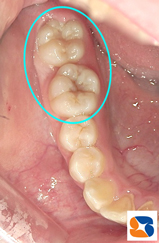

今回は、虫歯の予防についてのお話です。 写真の患者さんは、小学校5年生。永久歯の奥歯の溝が、茶色っぽく=写真左=なっていますね。 このままでは将来、虫歯になりそうで心配です。このような時、溝の中に材料名「シーラント」=写真右=を流し込み、青い光で固めます。歯を削らずに、そのままシーラントで溝を埋めるだけで虫歯の予防となります。あくまでも”予防”ですので、しっかり歯磨きは毎日、時間をかけておこなって下さいね。